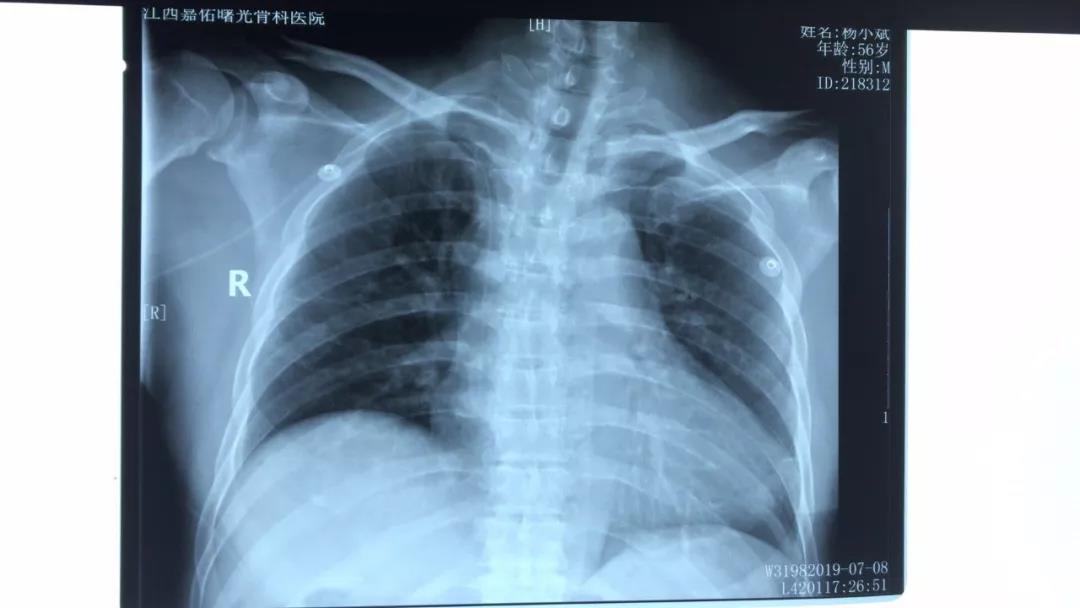

图为X线定位

PICC尖端理想位置在上腔静脉,当导管尖端不位于上腔静脉时,导管功能障碍及并发症的发生率将增加。置管过程中可通过超声探查颈内静脉避免导管异位,在不破坏最大化无菌区的情况下,及时调整导管位置,保证导管位于正确位置。